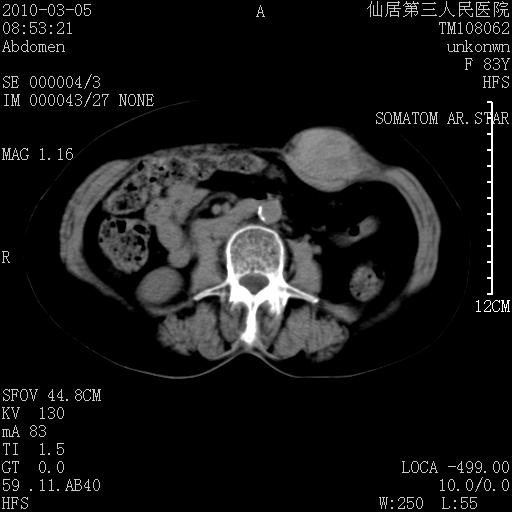

标题: CT24879:腹直肌病变。在线等。

女性,83y,腹痛一周。

考虑:左侧腹直肌神经纤维瘤可能

考虑左侧腹直肌血肿,肿瘤性病变待排。

增强看看,mfh可能性大,次之可考虑血肿、bfh、转移瘤、神经纤维瘤、侵袭性韧带样纤维瘤等。肝内钙化灶,右肾结石。

支持腹壁纤维肉瘤